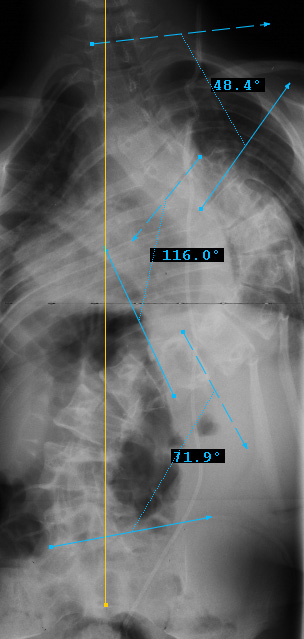

Preop LEFT Bend

Preop RIGHT Bend